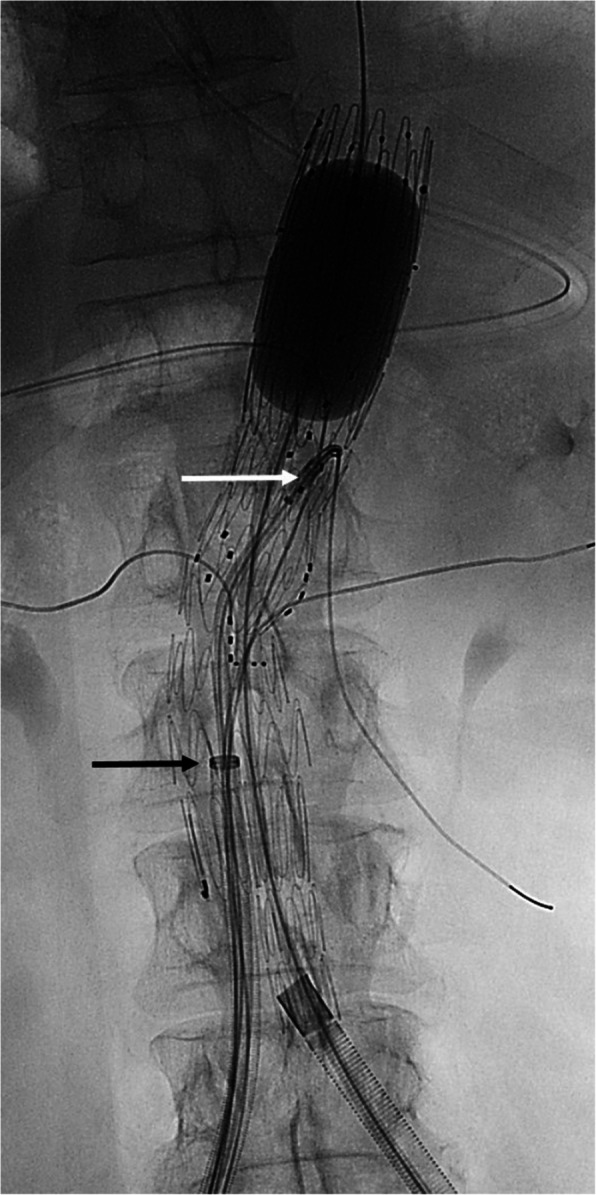

Background: The aim of this study was to compare the use of combined fenestrated and bifurcated aortic endografts to the standard modular design including a proximal fenestrated and a distal, bifurcated endograft. The combined design allows for a modification of the procedure that may contribute to lowering the risk of damaging the target vessel stents and reducing the perioperative obstruction of the ipsilateral access vessel.

Methods: Consecutive patients treated with fenestrated aortic repair between December 2020 and December 2022 were included in this retrospective, single center study. Technical success was analyzed, including the integrity of the target vessel (TV) stents assessed on perioperative CT. Further, the duration during which the large introducer had to be kept in the access vessel was analyzed. Finally, we report technical data on the endograft design, adverse events and midterm results.

Results: Twelve patients were treated with a modular endograft (group A) and 13 patients with a combined endograft design (group B). Technical success was 100% in both groups, however there were 4 deformed target vessel stents in group A, none in group B. The duration of potential flow reduction due to a large introducer in the access vessel was significantly shorter in group B than group A (median 54 min vs. 109.5 min, p < 0.05). No adverse events were reported in any of the groups. The observation period was shorter in group B (median 18 months vs. 33 months, p < 0.05). Except for one case of aneurysm growth in group A, all other patients in both groups showed stable or decreased aneurysm size without TV occlusions.

Conclusions: The integration of the bifurcation on the fenestrated endograft may contribute to the prevention of damage of the TV stents and has potential to reduce the duration of perioperative limb obstruction.